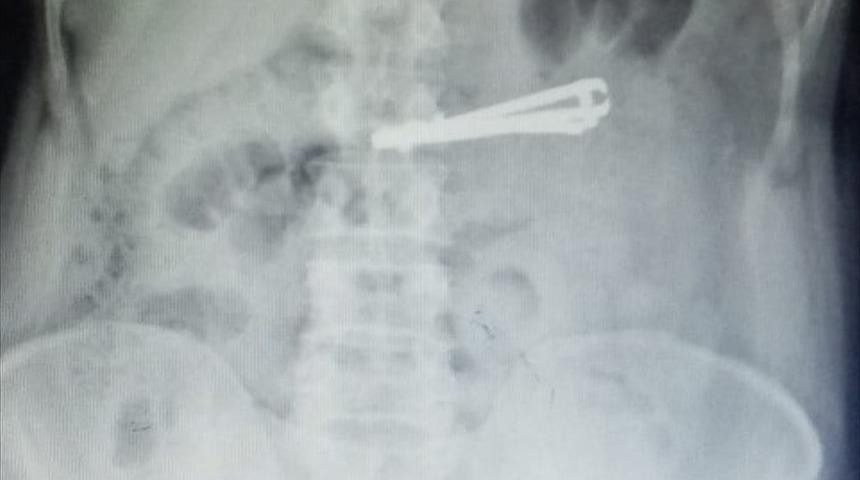

Siirt'in Kurtalan ilçesinde yaşayan ve doğuştan ağır mental retardasyon (zeka geriliği) hastası Mutih Akurt (42), elindeki tırnak makasını yuttu.

Hastanın midesindeki tırnak makası, Genel Cerrahi Uzmanı Dr. Yasemin Küçük'ün yaptığı endoskopiyle çıkarıldı.